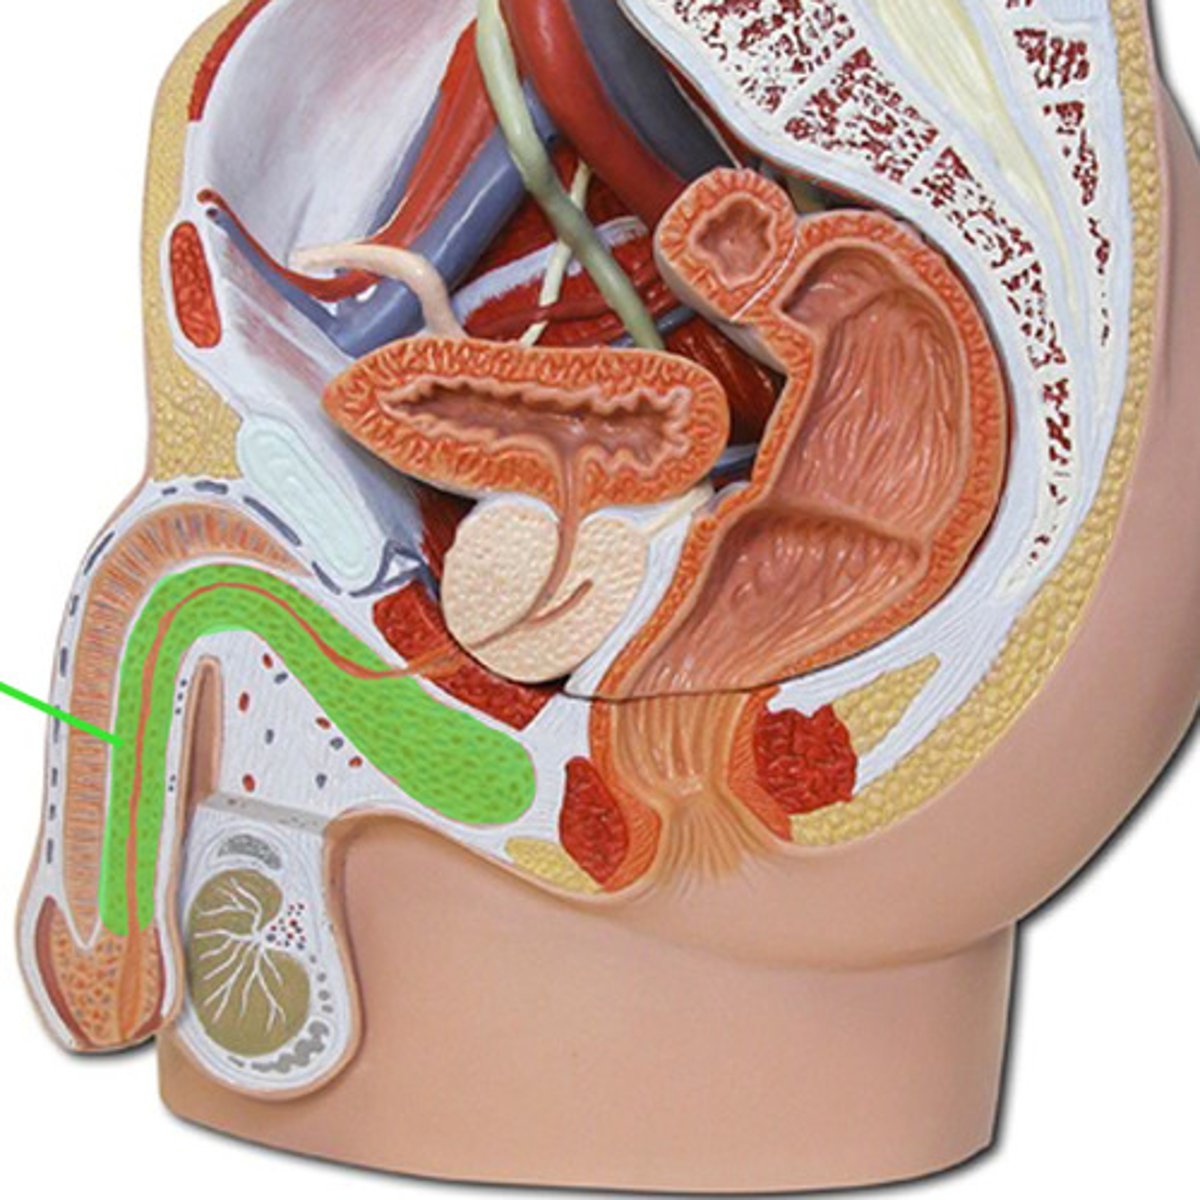

Ductus deferens

Urethra

Spongy urethra

Penis

Erectile tissue

Corpus cavernosum

Corpus spongiosum